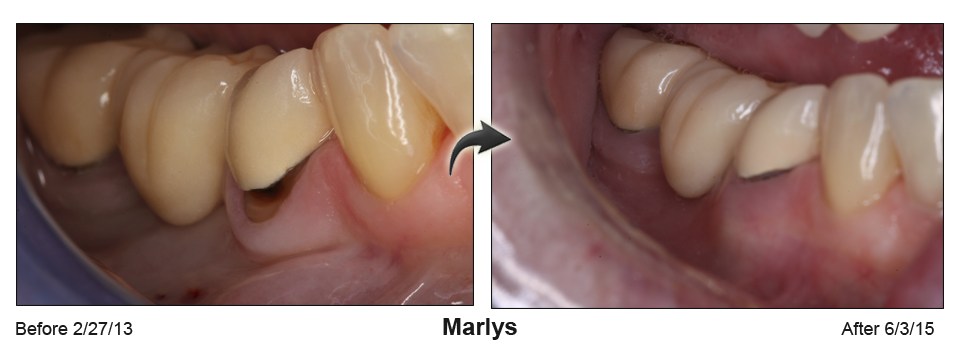

A rejuvenated smile and no sensitive roots

Gum recession not only ages your smile, it creates causes painful sensitivity to temperatures and sweets. Based in Houston & Baytown, TX, Dr. Khalid uses minimally invasive microsurgical techniques to perform cutting edge gum recession treatment and gum grafts.

Receding gums can make anyone look older

Receding gums can make anyone look older, often cause tooth sensitivity and may lead to tooth loss. Gum recession can be caused by excessive tooth brushing, gum disease or the normal aging process.

"Many people are unaware of the condition until their teeth become sensitive to cold temperatures because of root exposure. Others may be concerned by the unsightly appearance of their receding gums." says Dr. Khalid.